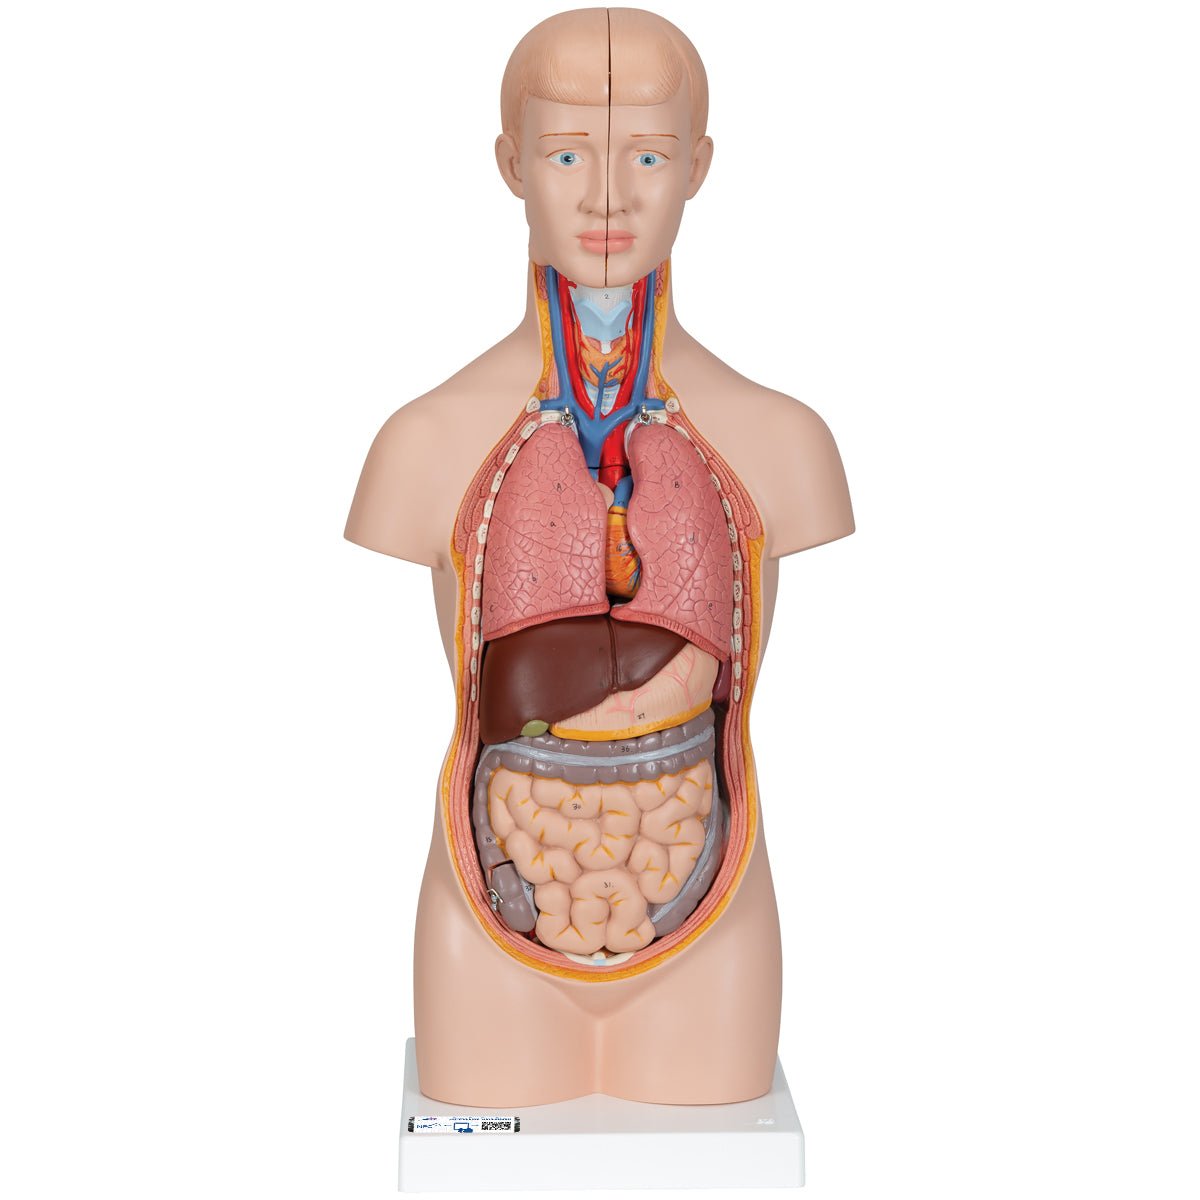

Salg af anatomiske modeller er det bærende element i eAnatomi, selvom vi også bruger mange ressourcer på at udvikle vores egne anatomiske materialer som fx plakater. Anatomiske modeller anvendes til forskellige formål og kan både vise afgrænset væv, organer samt organsystemer. Søger du en simpel model af knoglevæv eller måske en avanceret torso-model baseret på MRI teknologi, kan du finde det hele på eanatomi.com.